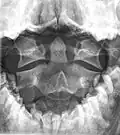

Type 2 dens fracture

Axis on X-ray taken through an open mouth, teeth visible